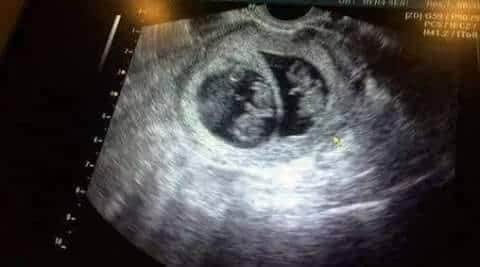

ULTRASON